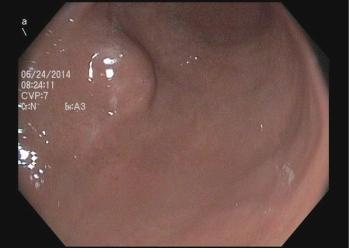

The incidental finding was noted during screening endoscopy for Barrett's esophagus. Can you answer these 3 questions on next steps and management of the case.